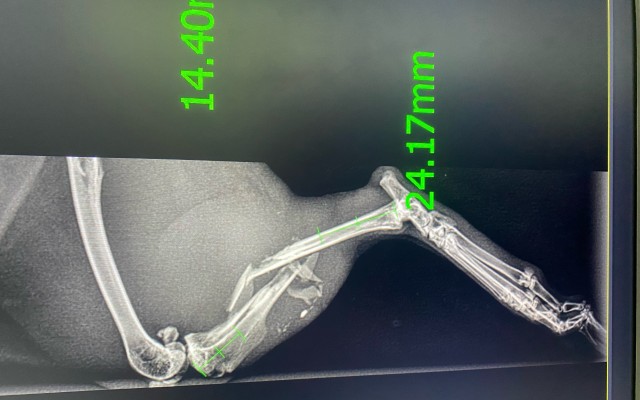

Pomohli jste přispět na operaci zlomené králičí nožky